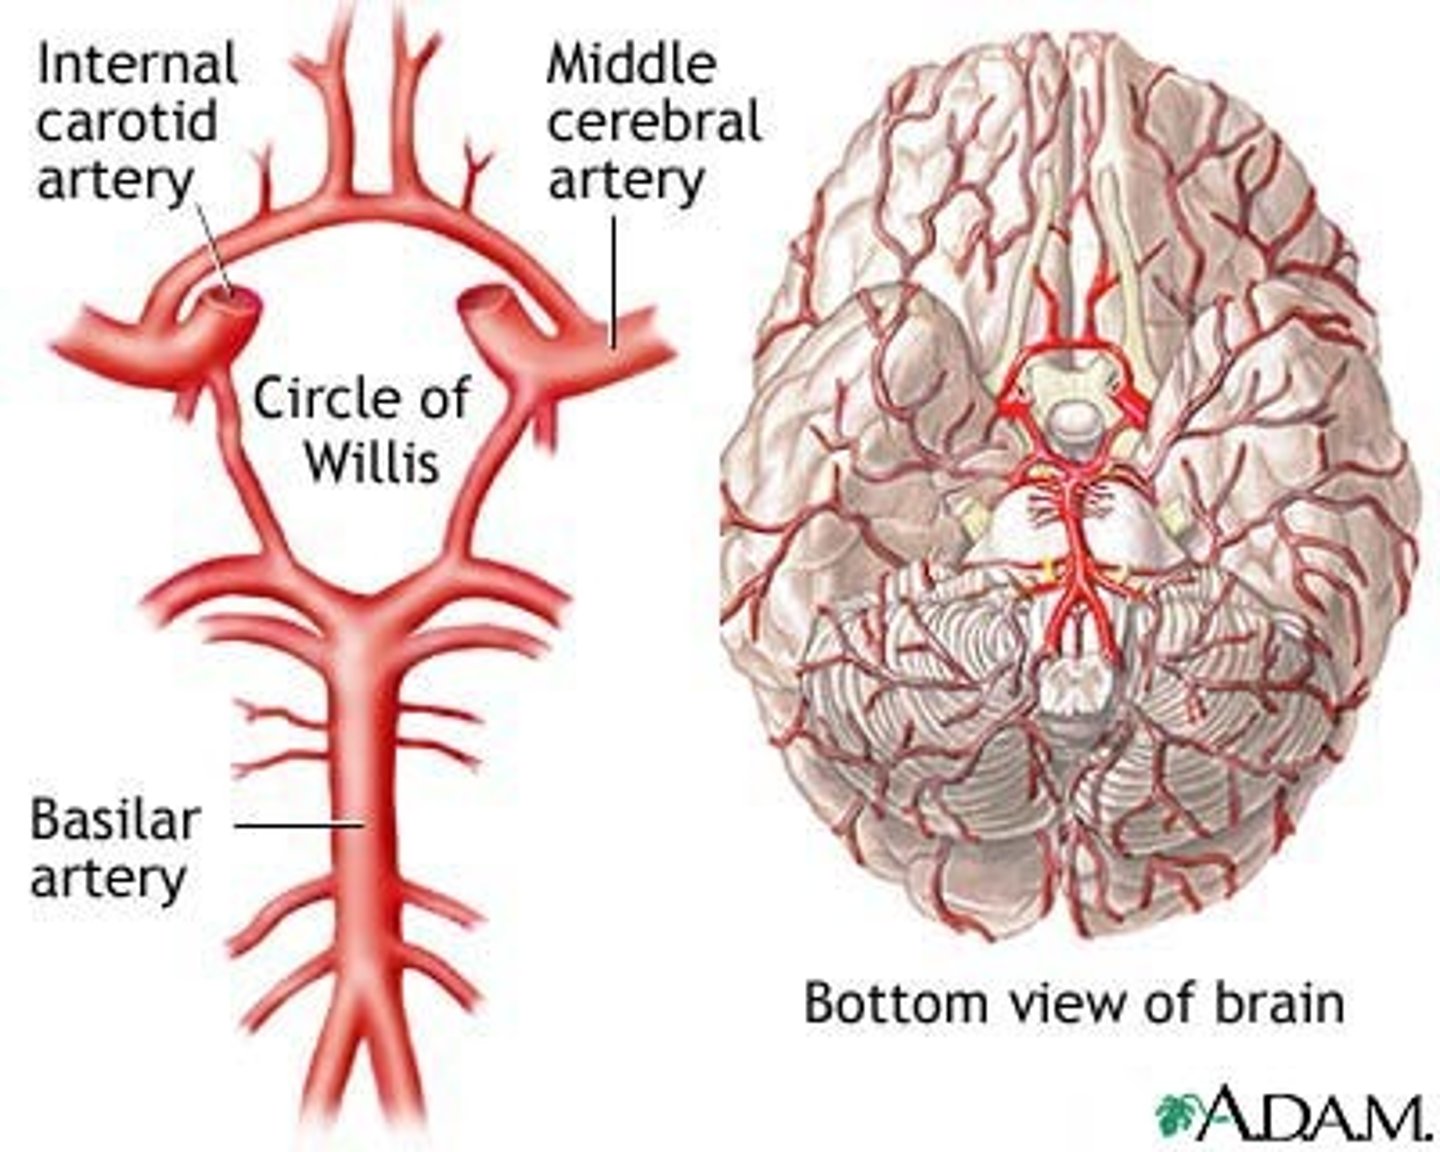

Blood supply to the brain

1) The brain is only 2% by weight but uses 20% of O2 consumption via carotid and vertebral arteries,

2) Nerve cells cannot store glucose or energy compounds like muscle tissue,

3) Interrupted blood flow to the brain can cause unconsciousness or irreversible brain damage if maintained for extended period of time

Cerebrovascular Accidents (CVAs and Strokes)

1)Death of brain tissue because of blood depravation,

2) Causes: Hemorrhagic & Ischemic

3) The glutamate cascade which lead to neural frying

-Rationale for rapid treatment